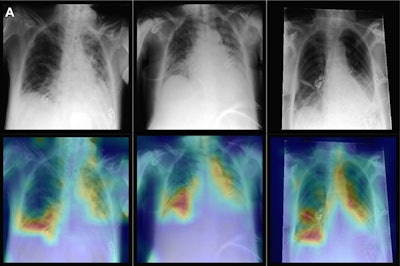

Representative radiographs (top), acquired in anteroposterior projection in the supine position, and corresponding attention maps (bottom). (A) Images show main diagnostic findings of the internal data set in a 49-year-old male patient with congestion, pneumonic infiltrates, and effusion (left); a 64-year-old male patient with congestion, pneumonic infiltrates, and effusion (middle); and a 69-year-old female patient with effusion (right). Image courtesy of Radiology.